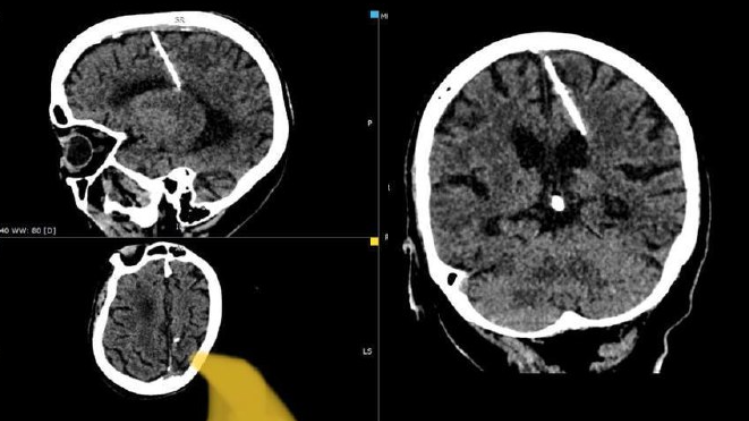

Comme il est possible de l’observer sur les photos du scanner, un objet fin traverse le crâne de la femme de part et d’autre. Les médecins estiment que sa survie est tout simplement incroyable.

Les médecins ne vont pas toucher à l’aiguille ou tenter de la retirer. «L’aiguille a pénétré dans le lobe pariétal gauche, mais cela n’a pas entraîné les conséquences attendues: la jeune fille a survécu», a relaté le ministère. La vieille dame n’étant pas immédiatement en danger, malgré le corps aiguisé planté dans son cerveau, les médecins ont jugé qu’il valait mieux laisser l’aiguille là où elle était pour «éviter d’aggraver son état». En revanche, la vielle dame sera surveillée de près, à l’avenir.